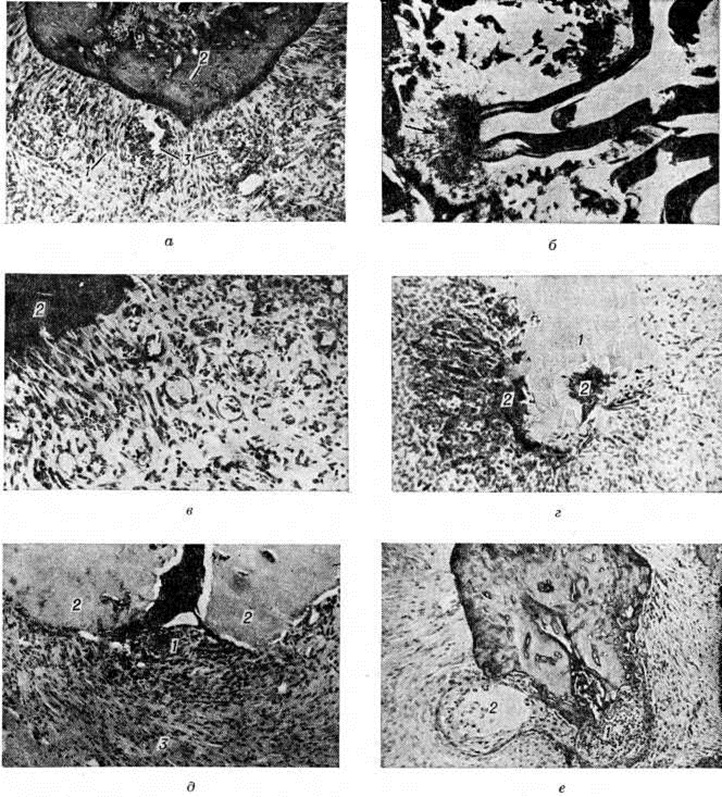

Рис. 1.

Микропрепараты верхушечного периодонта: а — при остром серозном экспериментальном периодонтите: 1 — ткани периодонта, пропитанные серозным экссудатом, 2 — верхушка корня зуба, 3 — периваскулярные скопления лейкоцитов; окраска гематоксилин-эозином; × 90; б — при гнойном экспериментальном периодонтите; стрелкой указан крупный абсцесс у верхушки корня зуба; окраска гематоксилин-эозином; × 40; в — при хроническом гранулирующем экспериментальном периодонтите: 1 — грануляционная ткань с хорошо развитыми сосудами капиллярного типа, 2 — узурированный край цемента корня зуба; окраска гематоксилин-эозином; × 90; грамм — при хроническом гранулирующем экспериментальном периодонтите: 1 — резорбция верхушки корня зуба, 2 — грануляционная ткань, замещающая твёрдые ткани зуба; окраска гематоксилин-эозином; × 90; д — при хроническом гранулематозном экспериментальном периодонтите: 1 — простая гранулема, 2 — верхушка корня зуба, 3 — фиброзная капсула; окраска гематоксилин-эозином; × 90; е — при хроническом гранулематозном периодонтите: 1 — сложная гранулема, 2 — формирующаяся эпителиальная киста; окраска гематоксилин-эозином; × 90.

Как правило, периодонт в отдельных участках пропитан серозным экссудатом с небольшой примесью лейкоцитов и круглоклеточных элементов. Лишь местами обнаруживают преимущественно периваскулярные компактные скопления лейкоцитов (рисунок 1, а). Прогрессирование серозного Периодонтит обусловливает его переход в гнойный Периодонтит, при котором макроскопически в утолщённом и полнокровном периодонте видны желтоватые очажки — гнойнички. В случае гнойного расплавления периодонта на поверхности корня зуба сохраняются лишь отдельные его фрагменты, остальная часть корня обнажена, покрыта гноем. Нередко в области больного зуба наблюдают воспалительную гиперемию и отёк надкостницы альвеолярного отростка и слизистой оболочки десны. Микроскопически в толще периодонта, окружающего верхушку корня зуба, на фоне резкой гиперемии видны очаговые и диффузные лейкоцитарные инфильтраты. Как правило, наблюдаются множественные микроабсцессы, в результате слияния которых в около-верхушечной области образуются более крупные абсцессы (рисунок 1, б). Обычно вокруг абсцесса формируется зона перифокального серозного воспаления, которая в виде пояса отграничивает абсцесс от окружающих тканей. В других случаях отмечается распространение серозно-гнойного и гнойного процесса на прилежащие участки костной ткани. При этом патологический процесс сопровождается незначительной либо умеренной резорбцией костной стенки зубной альвеолы, а также цемента корня зуба. Острый Периодонтит в некоторых случаях переходит в хронический.

В зависимости от характера тканевой реакции различают гранулирующий, гранулематозный, фиброзный и обострившийся хронический Периодонтит При гранулирующем Периодонтит макроскопически на отдельных участках верхушки корня удалённого зуба видны обрывки сочной темно-красного цвета грануляционной ткани. Поверхность корня неровная, шероховатая, с единичными либо множественными узурами. Микроскопически в окружности верхушки корня зуба обнаруживается не имеющее чётких границ разрастание грануляционной ткани на различных стадиях созревания (рисунок 1, в). В области разрастания грануляционной ткани наблюдается интенсивная резорбция твёрдых тканей корня зуба (цемента и дентина), а также костной стенки зубной альвеолы (рисунок 1, г). Грануляции замещают собой костную ткань и в отдельных случаях, резорбировав компактное вещество кости челюсти и разрушая надкостницу, прорастают в около-челюстные мягкие ткани. Наряду с рассасыванием твёрдых тканей зуба и кости но периферии воспалительного очага наблюдается и их новообразование. В прилежащих к воспалительному очагу участках костной ткани повсеместно выявляют гиперемию, отёк, очаговые и диффузные лимфогистиоцитарные инфильтраты. Происходит замещение костного мозга соединительной тканью.

Макроскопически зубные гранулемы имеют вид шаровидного или овального образования, окружённого плотной фиброзной оболочкой, обычно с гладкой поверхностью, припаянного к верхушке корня зуба, благодаря чему гранулема нередко извлекается вместе с удалённым корнем. Окраска зубных гранулем различна — от светло-жёлтой до темно-красной. Простая зубная гранулема микроскопически характеризуется образованием фокуса созревающей грануляционной ткани, отграниченного по периферии фиброзной капсулой различной толщины (рисунок 1,д). Усиление продуктивного компонента патологический процесса в периодонте сопровождается стиханием перифокальной воспалительной реакции в прилежащей костной ткани. В окружности зубной гранулемы наблюдается построение новых костных трабекул.

Кистогранулема (околокорневая киста) образуется из сложной зубной гранулемы в результате вакуольной дистрофии и распада эпителиальных клеток в центральных отделах эпителиальных тяжей, где наблюдается развитие мелких щелевидных просветов, при слиянии которых постепенно образуется полость, обычно выстланная изнутри эпителием, расположенным на подлежащей грануляционной ткани (рисунок 1, е). Фиброзная стенка кистогранулемы спаяна с периодонтом поражённого зуба (смотри полный свод знаний Зубная киста).